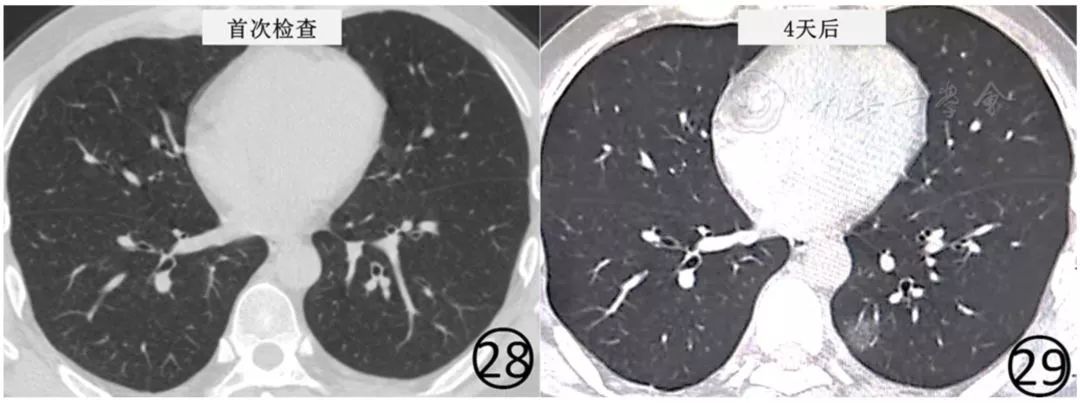

①新型冠状病毒核酸检测阳性,但是首次放射学检查阴性,复查时则发现肺内有异常表现(图28,图29);

图28,29 男,44岁,有流行病学史,发热1d,体温38.0℃,伴咳嗽、干咳、全身乏力。基线(图28)CT扫描肺内未见异常,新型冠状病毒检测阳性。4d后(图29)复查CT,显示左下肺后段可见磨玻璃阴影

①临床表现典型、新型冠状病毒核酸检测阳性的初诊患者,初诊胸部CT阴性,推荐3~5d复查胸部CT,观察有无病变出现;